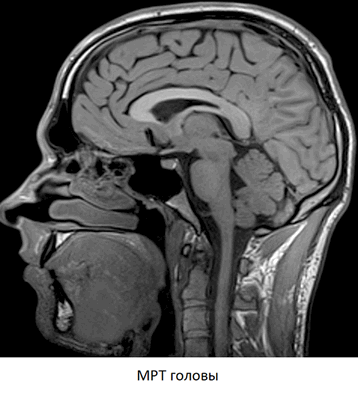

МРТ головы и шеи, что показывает

МРТ головы и шейного отдела позвоночника — метод диагностики болезней головного мозга и шеи. Процедура может проводиться в стандартном режиме, для исследования мягких тканей, или в ангио-режиме, для исследования кровеносных сосудов, кровоснабжающих центральную нервную систему. В основе метода — использование магнитных полей и радиоволн для получения послойных снимков области интереса с превосходной четкостью и детализацией.

Что показывает МРТ головы и шеи

Каждый МРТ снимок головы и шейного отдела позвоночника — это послойное изображение исследуемой области, сделанное в нескольких плоскостях. На нем четко различимы все анатомические структуры — головной и спинной мозг, нервы, кровеносные сосуды, мышцы, суставы и т.д. Метод позволяет сделать прижизненные снимки человеческого тела с высокой четкостью и самыми мельчайшими подробностями.

Расшифровывая снимки, врач-рентгенолог обращает внимание на малейшие признаки болезни. МРТ прекрасно “видит” воспаление, отек, нарушения кровообращения, опухоли и другие типовые патологические процессы. Это единственный на сегодняшний день метод, которые позволяет диагностировать практически все болезни головы и шейного отдела позвоночника за один раз.